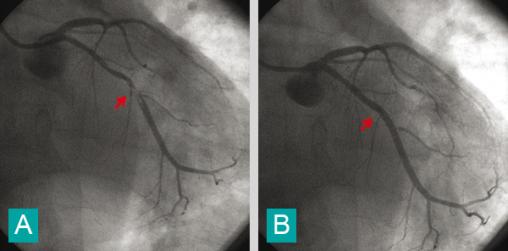

Coronarographie d'un patient ayant un syndrome coronaire aigu avec sous-décalage de ST et élévation de troponine.Les flèches rouges indiquent la présence d'une sténose coronarienne serrée avec volumineux thrombus intraluminal (A), et la disparition de la lésion après angioplastie avec pose d'une endoprothèse coronarienne (B).